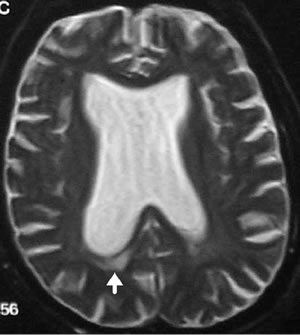

由于四脑室出口狭窄引起的脑积水小脑功能障碍,患有脑积水的3岁男孩。A、B为其术前影像,C、D显示内镜下三脑室造口术成功控制脑积水,术前症状迅速消退。